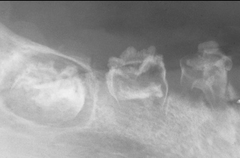

-obstruction in the gland hard nodule in soft tissue at a salivary gland -calcification of material -can be seen radiographically